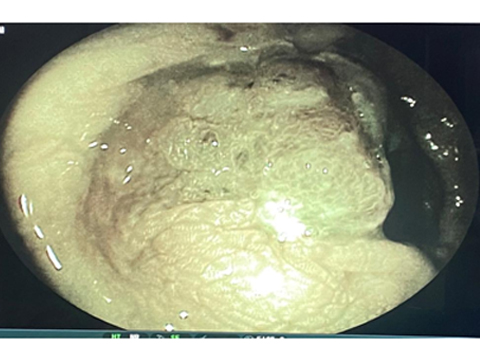

HIGH DEFINITION ENDOSCOPY WITH FICE TECHNOLOGY SHOWING A CANCEROUS LESION